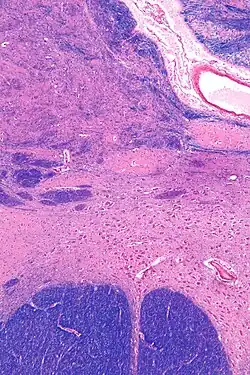

MRI showing a coronal plane of the head with marks showing the location of the substantia innominata, the region in which the nucleus basalis is found. | |

![]() Intermediate magnification micrograph of the nucleus basalis. LFB-HE stain. | |